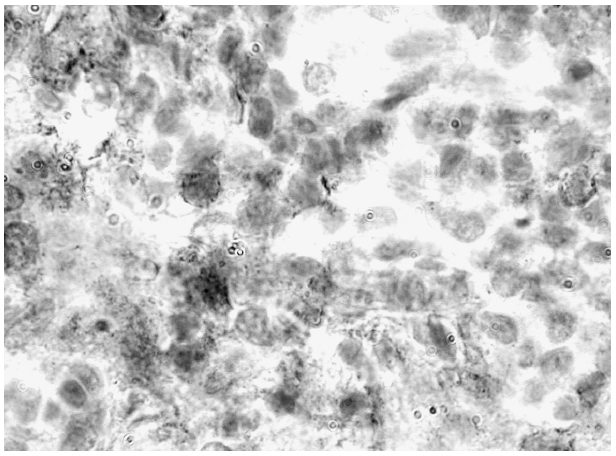

Иммунная активация лимфоцитов при ВИЧ-инфекции приводит к апоптозу Т-клеток, который рассматривается как один из механизмов истощения популяции CD4+- Т-лимфоцитов [12]. В наших исследованиях в участках склероза: в субкапсулярной зоне, вдоль разрастающихся трабекул и в области ворот лимфоузла определялись скопления лимфоцитов, у которых наблюдались изменения формы ядер с конденсацией хроматина, или фрагментация клеток с образованием апоптотических телец. Иногда в участках склероза, особенно в субкапсулярной зоне, выявлялся так называемый «краш-феномен», при котором ядра лимфоцитов приобретали вытянутую форму в виде базофильных тяжей ядерного материала, напоминающих «струи» и «потоки». Такие изменения клеток описаны при мелкоклеточном раке, когда опухолевые клетки, становясь хрупкими, легко деформируются [1]. По мнению Ю.Р. Зюзя и соавт. [2], при ВИЧ-инфекции происходят апоптотические изменения клеток с последующим их некрозом. C. Doitsh и соавт. [14] установили, что Т-лимфоциты, пораженные ВИЧ, в лимфоузле погибают путем апоптоза через активизацию каспазы-3, в то время как лимфоциты, не пораженные вирусом, погибают путем пироптоза, при котором каспаза-1 нарушает целостность цитолеммы и вызывает некроз клетки. При этом выделяются ИЛ-1β и ИЛ-18, не только способствующие гибели большого числа лимфоцитов, но и запускающие воспалительную реакцию. В наших исследованиях апоптотические тельца в виде мелкой зернистости определялись в цитоплазме стромальных клеток и макрофагов, а также выявлялись между клетками стромы (рис. 3).

Формирование тотального склероза в лимфатическом узле в результате развития при ВИЧ-инфекции хронического воспаления сопровождается утратой фибробластических ретикулярных клеток, являющихся источником ИЛ-7 и других цитокинов, обеспечивающих пролиферацию и дифференцировку

Рис. 3. Стромальные клетки лимфоузла, дающие положительную окраску на CD4+ в виде зернистости, выявляемой в цитоплазме. ИГХ: СD4+. Ув. 10×100

лимфоцитов [11, 18]. Затруднение доступа Т-лимфоцитов к ИЛ-7 нарушает процесс их самоподдержания. В исследованиях D. Jacob и соавт. [17] показано, что фибробластические ретикулярные клетки создают в лимфоузле трехмерную сеть, обеспечивающую перемещение и взаимодействие лимфоцитов, и оптимальные условия для их контакта с регуляторными факторами. Изменение морфологии и связей между стромальными клетками, перестройка сосудистого компонента нарушают синтез и распределение цитокинов, факторов роста и других посредников, обеспечивающих миграцию лимфоцитов и эффективное формирование иммунного ответа. Более того, развитие склеротических процессов в лимфоузле при ВИЧ-инфекции приводит к гипоксии [15], создающей условия для гибели лимфоцитов. Гипоксия способствует неоангиогенезу, обеспечивающему усиленный приток лимфоцитов, в том числе Т-reg, которые синтезируют трансформирующий ростовый фактор β1(TGF-β1), активизирующий фибробласты к синтезу коллагена. Известно [4], что дефицит ИЛ-7 снимает его ингибирующее влияние на функцию Т-reg-лимфоцитов. Высокий уровень продукции TGF-β1 был обнаружен у зараженных вирусом иммунодефицита макак и у пациентов с ВИЧ-инфекцией, что сопровождалось усилением синтеза коллагеновых волокон в лимфоидной ткани [19]. Продукция факторов, способствующих развитию склероза в лимфоузлах, осуществляется также пораженными при ВИЧ-инфекции макрофагами [9], которые при взаимодействии с апоптотическими клетками активно продуцируют TGF-β1. Иммунная активация лимфоцитов в условиях гипоксии и дефицита регуляторных факторов в результате развития склероза приводит клетки к гибели. Массовая гибель лимфоцитов, наблюдаемая особенно в зонах склеротических изменений лимфоузла, возможно, является причиной значительного снижения концентрации Т-лимфоцитов в крови. В ранее проведенных [10] исследованиях с помощью проточной цитофлуориметрии установлено, что уменьшение числа лимфоцитов в периферической крови происходит за счет наивных CD4+-лимфоцитов. Дефицит CD4+-T-клеток индуцирует процесс гомеостатической пролиферации. Это может происходить как за счет влияния IL-7, так и за счет образования при разрушении клеток внеклеточной ДНК, циркулирующей во всех жидких средах организма [4]. Анализ экспрессии маркера Ki-67 показал, что деление наивных CD4+-T-клеток в лимфатическом узле протекает значительно более интенсивно по сравнению с кровью. Пролиферирующие лимфоциты, не получая дальнейших стимулов к дифференцировке в результате поражения стромальных клеток и развития склеротических процессов в лимфоузле, подвергаются гибели путем апоптоза или некроза, а «обломки» апоптотировавших элементов фагоцитируются стромальными клетками и тканевыми макрофагами. Таким образом, согласно современной концепции [12], высокий уровень гибели Т-лимфоцитов в лимфоузлах определяется не столько прямым действием вируса на Т-лимфоциты, сколько иммунной активацией CD4+-Т-лимфоцитов в результате действия разных факторов, в том числе и развитием хронического воспаления. Результатом воспаления является формирование склеротических процессов в лимфатическом узле, приводящих к нарушению взаимодействия лимфоцитов и стромальных клеток.

Массивная гибель лимфоцитов способствует активизации фагоцитарной функции стромальных клеток ПЛУ, и вся строма органа участвует в утилизации разрушающихся клеток. При иммуногистохимическом определении лимфоцитов, экспрессирующих маркер CD4+, слабое положительное окрашивание выявлялось лишь в лимфоцитах, расположенных в синусах лимфоузла. Во всех зонах ПЛУ, исключая мантийную зону ВФ, стенки сосудов и участки склероза, положительная реакция на CD4+-лимфоциты определялась в виде мелкой зернистости в цитоплазме стромальных клеток и макрофагов синусов (см. рис. 3). Создавалось впечатление, что осуществляется фагоцитоз стромальными клетками всех зон CD4+-лимфоцитов, подвергшихся массивному разрушению. Лимфатический узел, таким образом, становился «кладбищем» для гибнущих лимфоцитов. В результате в ПЛУ формируется замкнутый круг: развитие склеротических процессов в лимфоузле вызывает гибель Т-лимфоцитов, которые, в свою очередь, являются источником образования лимфотоксина-β [19]. Утрата CD4+-Т-лимфоцитов сопровождается дефицитом лимфотоксина-β и приводит к потере уже самих фибробластических ретикулярных клеток, которые через продукцию IL-7 поддерживают жизнедеятельность Т-клеток.